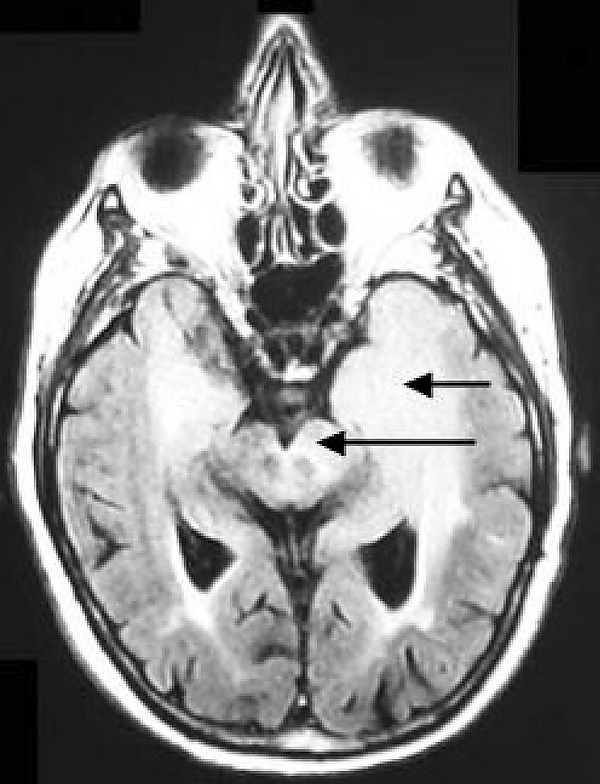

Глиоматоз головного мозга

Глиоматоз головного мозга - редкая разновидность диффузной глиальной опухоли, широко инфильтрирующая головной мозг, вовлекающая две и более доли (нередко билатерально) и часто распространяющаяся инфратенториально. Сам термин введен в обиход в 1938[1] году и с тех пор в литературе описано около 200 случаев. Несмотря на активные исследования данного заболевания и научные поиски, до сих остаётся неясным является ли глиоматоз формой диффузно-инфильтративной глиомы или же представляет собой самостоятельный патологический синдром.